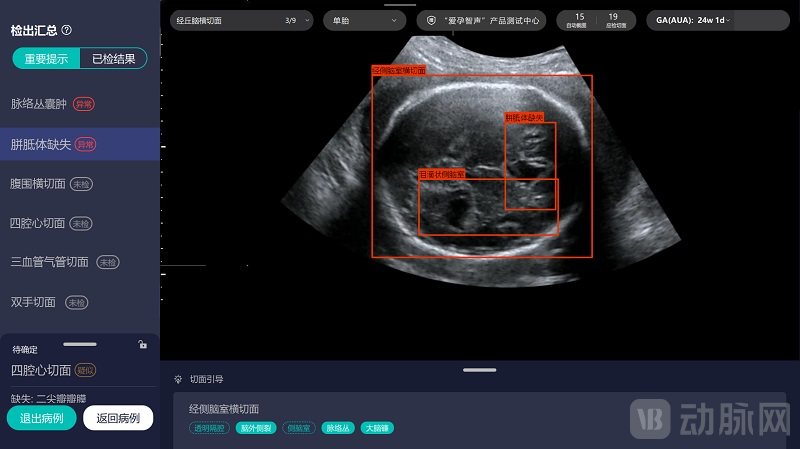

2018年,爱孕记首款爱孕智声产品推出,在科研合作单位中山一院进行相关学术研究。当时,正好有一位在中山一院会诊的患者,胎儿可能出现了胼胝体缺失(属颅脑畸形,可能对颅脑发育产生重要影响)。但是外省某三甲医院磁共振诊断结果指出胼胝体并无异常。担忧胎儿健康的患者慕名来到中山一院,在谢红宁教授进行超声影像诊断时,爱孕智声产品同步给出了“胼胝体缺失”的辅助诊断信息,最终通过专家诊断意见证实了爱孕智声产品辅助诊断信息是正确的。因为这件事情,让汪南更加看到了智能化产品的价值、坚定了决心,“我觉得这个事一定能成。”

实现了全流程多任务导航辅助。根据国内外指南对于产前超声标准切面的规范化要求,产前超声医师在产前筛查时,需要扫描并留存若干标准切面图像,但是以往扫描更多凭借超声医师的经验,可能出现遗漏等情形。爱孕智声产前超声动态影像导航系统则可以实时精确监测早孕期55种结构和中晚孕期101种结构是否检出、切面是否标准,实时智能指引操作者获取更标准切面,百分百防止漏筛漏检。

首创畸形诊断。与病理诊断揭示患者肿瘤良恶性不同,产前超声诊断更加注重父母担心的胎儿畸形问题。目前爱孕智声产品可实时智能化识别并精确提示指南要求的9种重大畸形及25种胎儿中枢神经系统异常,且敏感性和特异性均>95%。在广东省妇幼保健院举行的34家医院36名医生参与的一项研究表明,通过严谨的随机交叉试验设计,爱孕智声产品可以提升医生识别胎儿颅脑异常声像图6-10个百分点的敏感性(即降低漏诊率6-10个百分点)。